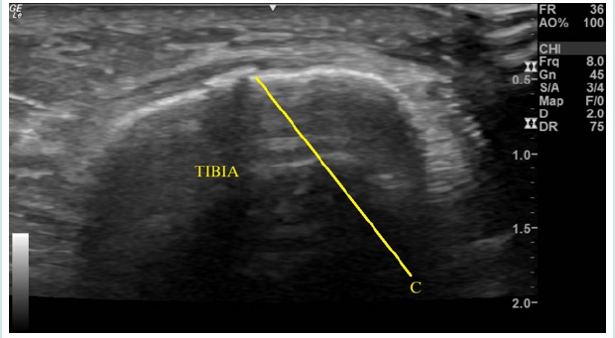

CM was a 67-year-old female runner presenting for an initial evaluation of left ankle and distal medial shin pain. Her pain was primarily present when running and she experienced a deep sharp pain in her shin, with a 5/10 score on the numerical pain scale (NPS). On physical exam, her tibia was tender to palpation with a small prominence over the distal medial aspect. She arrived to clinic with prior recent X-ray, ordered by her primary care physician. As seen in (Figure 1), her X-ray results were unremarkable for any pathology. Next, diagnostic MSK US was performed using the General Electric Logiq E R6 Portable Ultrasound machine, with a high-frequency linear transducer positioned over her area of tenderness on the distal tibial metadiaphysis. Her MSK US exam revealed a frank cortical break in the distal tibia, as seen in (Figure 2). Additionally, she experienced tenderness to sonopalpation. Due to a high clinical suspicion for a stress fracture, an MRI was ordered. She was recommended to strictly avoid weight-bearing activity for [5,7] days and was advised to avoid running for [4,6] weeks, with a gradual return to running through a walk-run program at physical therapy.

Figure 2: Musculoskeletal Ultrasound imaging moderate cortical irregularity (C) of the tibial metadiaphysis, visualized in shortaxis, with through sound transmission; suggestive of fracture at area of maximal intensity.